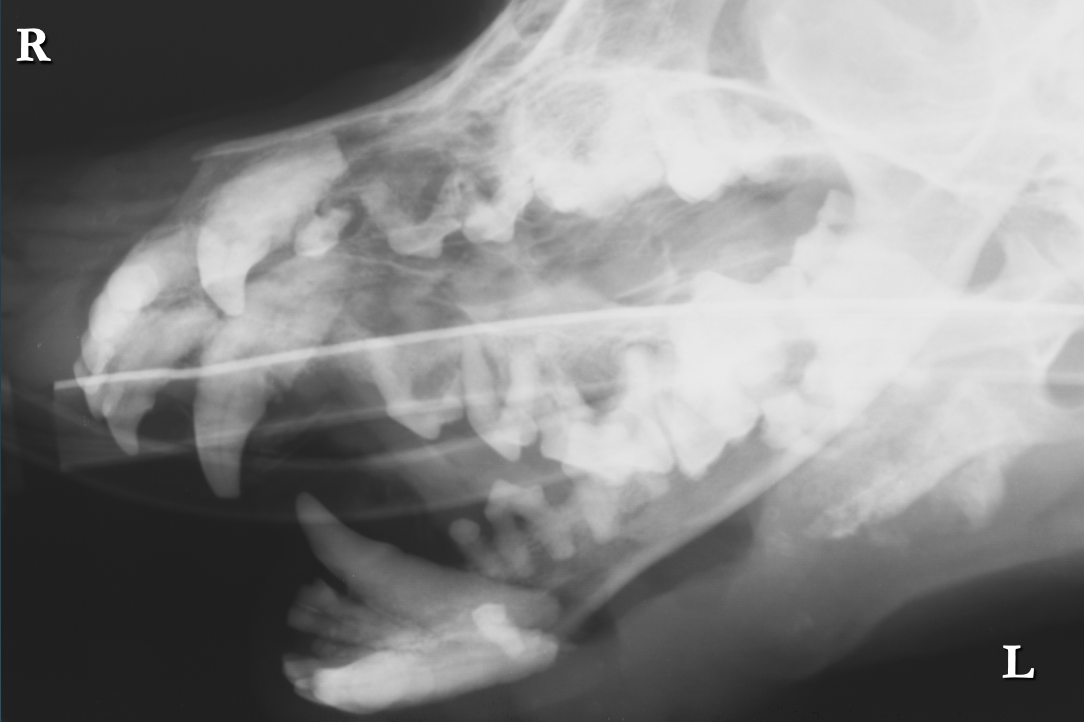

What is shown in this image?

A

osteosarcoma: